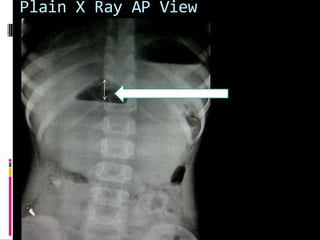

Plain X Ray AP View

Plain X RayAP View